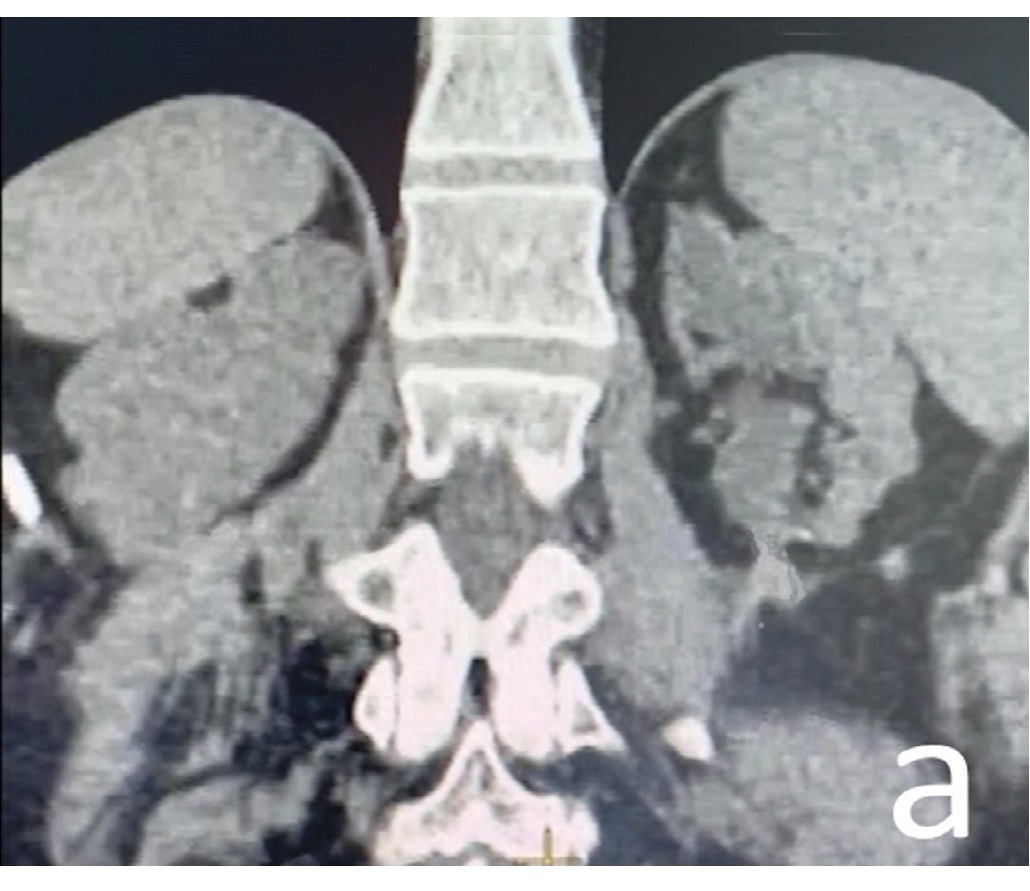

Раздел: Снимки-откровения